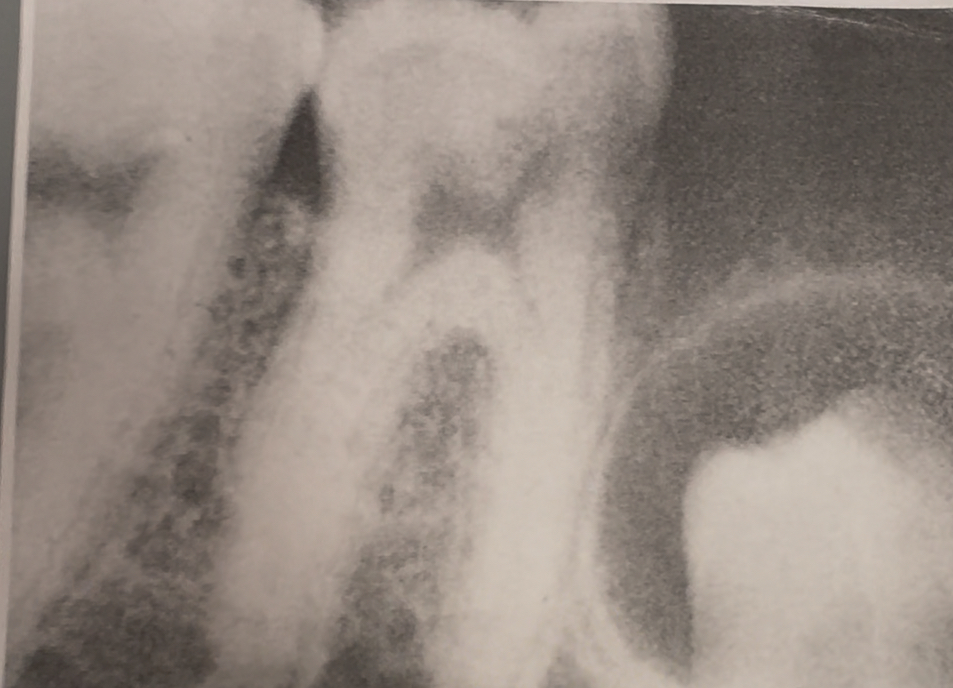

Endodontics

Involves the cause, diagnosis, prevention, and treatment of diseases and injuries to the pulp and associated structures

Oral maxillofacial radiology

Uses digital imaging to locate tumors and infectious diseases of the jaws, head, and neck, and assists in the diagnosis of patients with trauma and temporomandibular disorders

film exposed twice/double exposure

two different images

patient movement

film placed backwards; herringbone

unexposed film

exposed to white light

overexposed

underexposed

incorrect film placement

incorrect horizontal angulation/ overlap

vertical angulation too steep/foreshortened

verticlal anglulation too flat/ elongation

film excessively bent

Impaction in mixed dentition |

Impacted third molar |